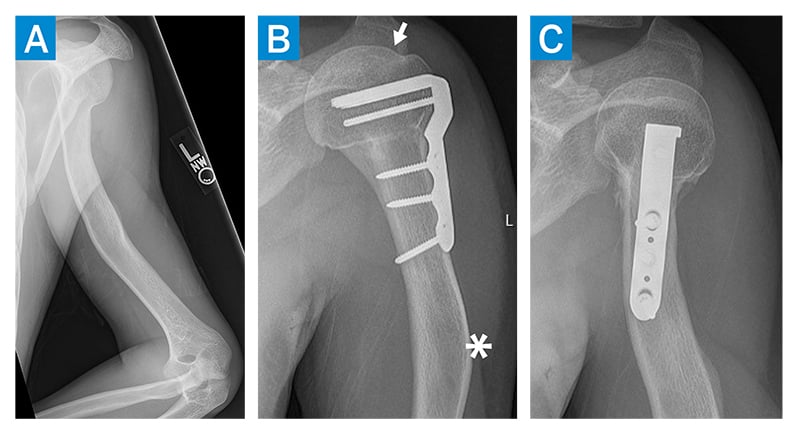

Figure 4: Preoperative radiograph (a) showing a complex multiapical deformity of the left humerus, with proximal humerus varus and ER and extension bowing deformities at the diaphysis. AP (b) and IR (c) radiographs at 6 months postoperative reveal a healed osteotomy, with restoration of the normal proximal humeral geometry. The articular margin was now proximal to the greater tuberosity (arrow), with residual bowing deformity of the shaft (asterisk).